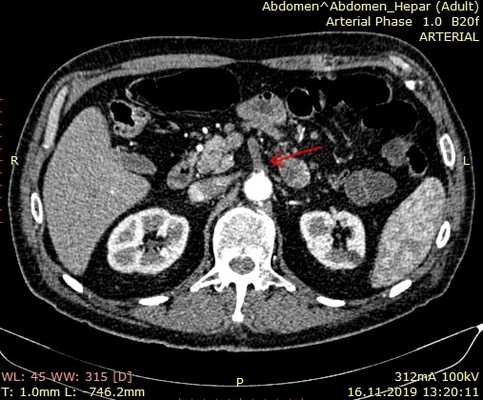

При обзорной рентгенографии брюшной полости определяется пневматизация кишечника, наличие горизонтальных уровней жидкости в брюшной полости. Специфическим методом диагностики острой окклюзии мезентериальных сосудов является селективная мезентерикография, которая уже на ранней стадии заболевания может выявить отсутствие кровотока в стволе и ветвях брыжеечной артерии. При наличии технической возможности выполняется магнитно-резонансная ангиография мезентериальных сосудов.

Мультиспиральная компьютерная томография с ангиографией

Мультиспиральная компьютерная томография аорты и ее ветвей позволяет точно оценить состоянии брыжеечных сосудов и помочь правильной постановке диагноза. Признаками острой мезентериальной непроходимости является отсутствие контрастирования брыжеечных артерий со слабым развитием коллатеральных сетей кровообращения. При соответствующих жалобах и клинической картине компьютерная томография позволяет поставить точный диагноз в большинстве случаев мезентериального тромбоза. Требуется внутривенное введение контраста и детальный анализ полученных изображений.